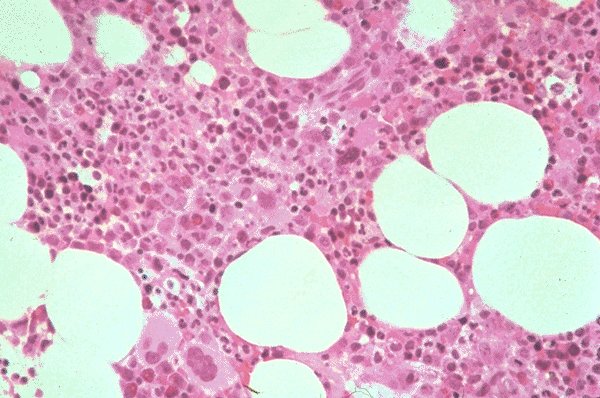

This bone marrow biopsy is stained with H&E and

is shown at low power magnification. The general

cellularity is normal and a few larger

megakaryocytes are appreciated. The remainder

of the morphologic characteristics of the cells are

somewhat more difficult to appreciate at this

power.